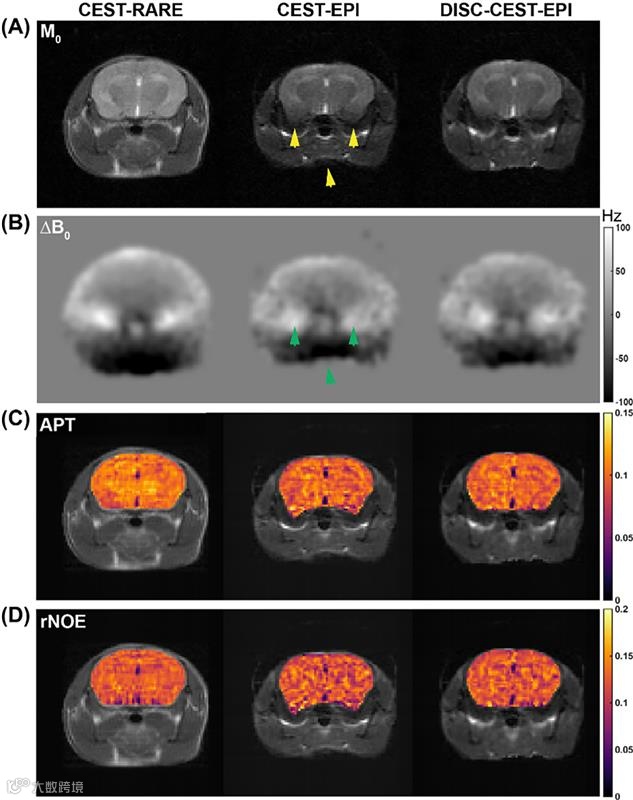

失真通常是快速EPI技术的必然代价。这项开放获取研究提出了一种智能解决方案:利用Z谱本身生成场图,实现单次激发CEST-EPI的自校正——无需单独采集场图即可简化工作流程。在模型和鼠脑实验中,该方法(DISC-CEST-EPI)显著提升了成像质量,尤其在3T场强下,有效提高了SSIM值及CEST定量分析的可靠性。这对临床与前临床MRI均是利好消息——在追求速度且易受畸变影响的场景中尤为重要。

在3T场强下,以具有弛豫增强的CEST快速采集作为参考标准时,DISC-CEST-EPI在体外和体内实验中均展现出高于CEST-EPI的SSIM值和空间一致性。在11.7 T活体实验中,DISC-CEST-EPI的酰胺质子转移图谱与中继核Overhauser效应图谱的SSIM值略高于CEST-EPI,且与场映射及顶部增强技术相当。

DISC-CEST-EPI技术可校正3T场强下CEST-EPI的失真现象,从而提升SSIM值并优化CEST定量分析。该方法有望在低场强MRI环境下显著改善单次激发CEST-EPI的成像质量与诊断准确性。然而,DISC-CEST-EPI在11.7 T场强下的性能表现受限,需进一步研发以增强其在超高场强环境下的应用效能。